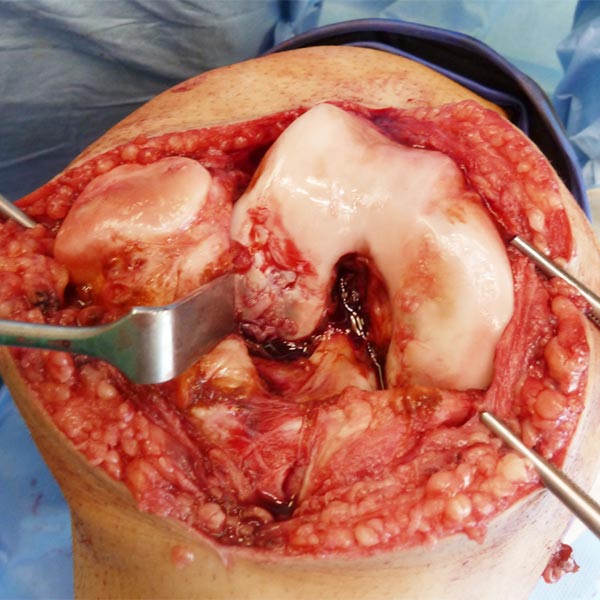

Intraoperatives Bild nach Entfernung der Synovia sowie der intraartikulären venösen Malformation. Noch vorhandene Reste der venösen Malformation über dem vorderen Kreuzband. Ausgedehnter, flächiger Knorpelschaden am lateralen Femurkondylus.

Die venöse Malformation wurde ganz entfernt, das vordere Kreuzband ist jetzt wieder voll sichtbar. Der Knorpelschaden wurde durch eine sog. Extrazelluläre Matrix gedeckt und behandelt.